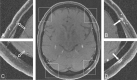

Fig 3.

3T transversal contrast fat-suppressed T1-weighted SE image acquired with the large FOV that covers the entire cranial circumference. Enlargements of the temporal branch of the superficial temporal arteries (A and B) and of the superficial occipital arteries (C and D) demonstrate the cranial involvement pattern. Mural thickening and inflammatory changes are depicted in the left temporal artery (enlargement B, 0.7-mm mural thickness, rated as “3”) and occipital artery (enlargement D, 0.7-mm mural thickness, rated as “3”), whereas the right-sided arteries display no signs of mural inflammation (enlargements A and C, 0.2-mm mural thickness, both rated as “0”). Temporal artery biopsy validates GCA in this patient.